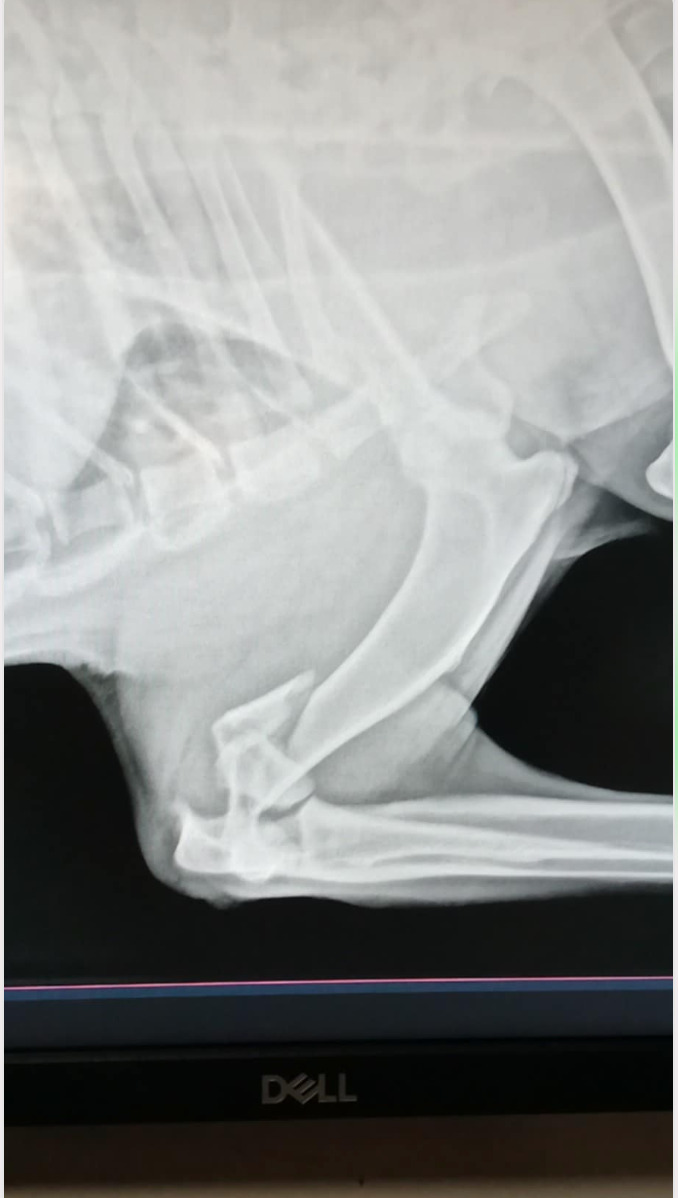

Woofy has politely allowed to be petted, even while in excruciating pain. He was overheated from staying in the back of the car and in the yard, but despite his condition, he was not aggressive or reactive. He had to be sedated to get his xray done, and the images were immediately sent to Dr. Hanson at Nederland, one of the best in his profession whom we trust immensely. Dr. H concluded that the fracture is in the humerus at the elbow and involves the cartilage in the joint. There are also multiple broken pieces that make it a complicated surgery. The estimate is below.

If the repair surgery is not done within a day or two, he will need to amputate his arm.

Now that the bruises have been healing, he could do another xray yesterday and informed us that, to avoid amputation, we have to put another plate to hold the first plate, as it has luxated out of position due to him moving so much. He said we can ride it out with one plate and see if it works but he will have to be amputated if it doesn't work, but he feels that his chances of saving the leg increases if he can put the second plate.

Thursday, Aug 29 - today is one week from his surgery and Woofy came to us with so many bruises and inflammation that Dr. Hanson, his orthopedic surgeon was unable to see through all the fractures and broken bones.